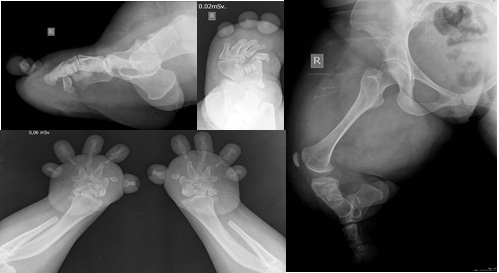

Síndrome de Grebe. Reporte de un caso. [Grebe syndrome. Case report.]